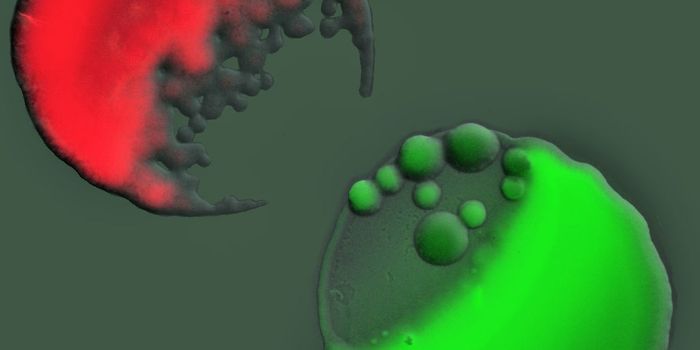

JUN 02, 2016Cell & Molecular BiologyMitochondrial replacement therapy was hailed as a promising new way to overcome diseases passed down in the DNA of mitoc ...